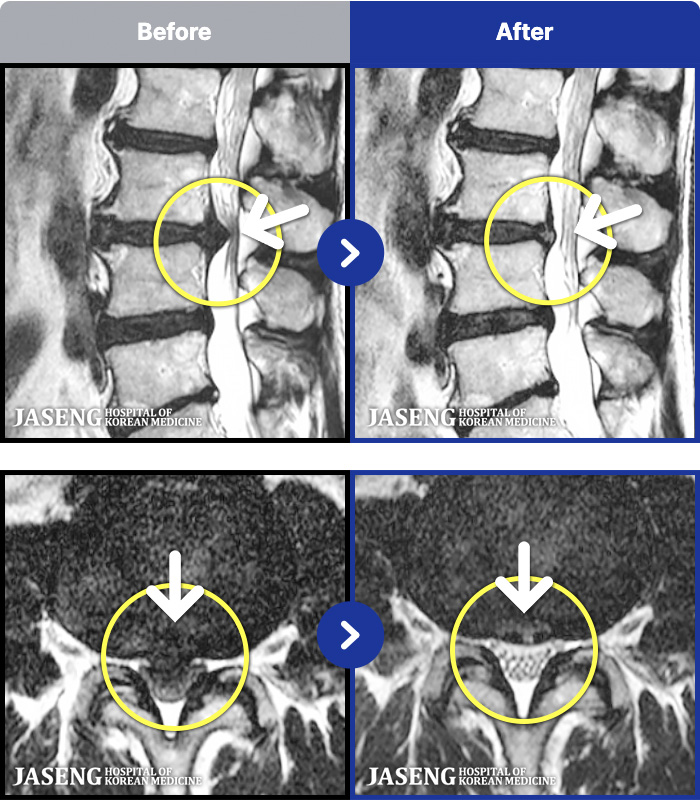

188 MRI ũ ʸ Ȯϼ.

ȯںп Ǹ ǿ ԿǾ, ο ġ ۿ Ƿ ġḦ Ͻñ ٶϴ.